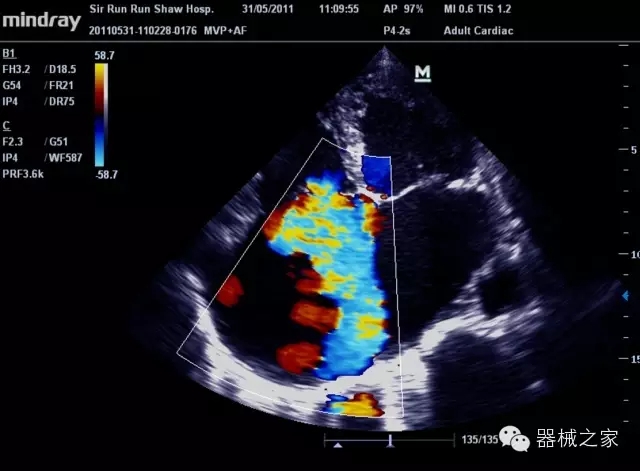

經(jīng)典產(chǎn)品:M7(星鉆)

臨床圖片賞析

產(chǎn)品特點(diǎn)

·優(yōu)秀的圖像效果、強(qiáng)大的功能體驗(yàn)、豐富的探頭選擇、合理的便攜式設(shè)計(jì),全中文顯示及病人管理界面,使得M7在任何場合、任何時(shí)候都能快速響應(yīng)更好的心血管、腹部、婦產(chǎn)、小器官等常規(guī)超聲檢查以及肌骨、神經(jīng)、顱腦、術(shù)中等新興領(lǐng)域的使用需求;

8倍波束并行處理系統(tǒng)

·在便攜式緊湊平臺(tái)上采用更多倍波束并行接收信號(hào)處理模式,無論二維還是彩色血流圖像狀態(tài)下,擁有更靈敏的回波頻移捕獲能力,大大提高時(shí)間分辨率,尤其使得心血管表現(xiàn)更為突出;